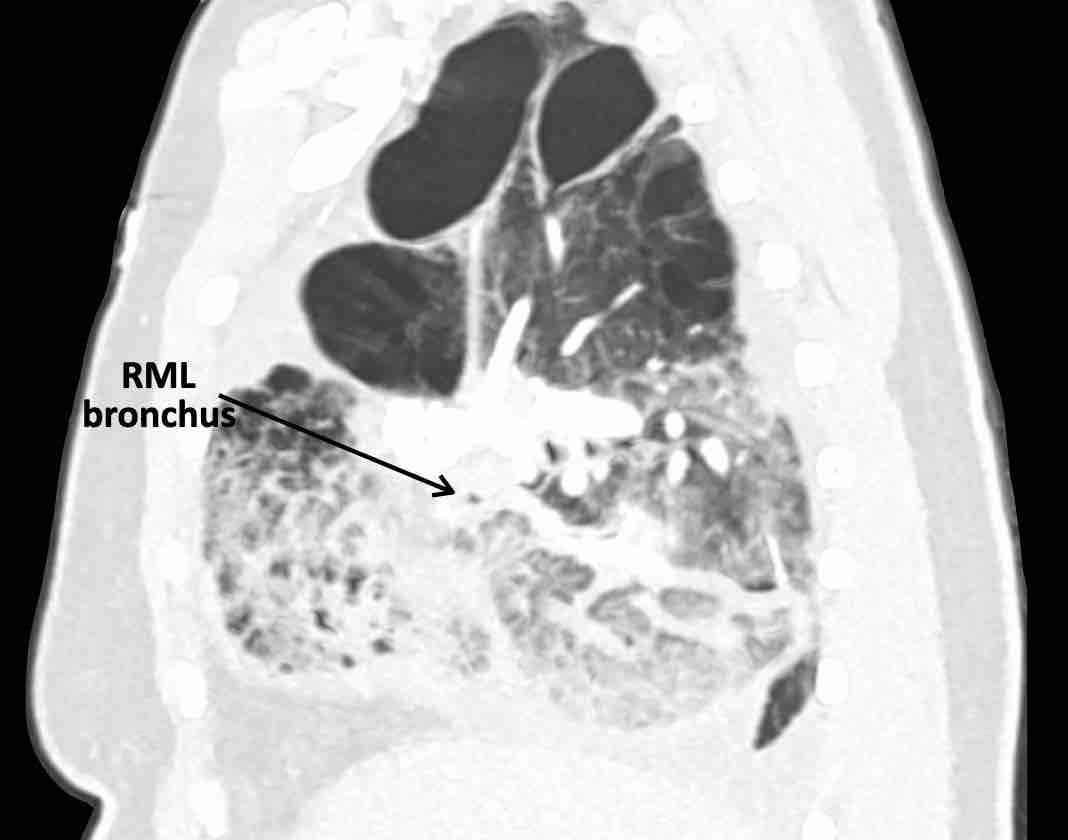

Các hình ảnh này của một bệnh nhân nữ 65 tuổi sau khi đã cắt thùy trên phổi phải trước đó.

Theo dõi lần lượt các phế quản giúp xác định mỏm cắt thùy trên phổi phải (RUL), phế quản thùy giữa bị tắc nghẽn và các phế quản thùy dưới còn thông.

Điều này xác định mô phổi bị di lệch xuống dưới chính là thùy giữa phổi phải (RML), thấy rõ nhất trên mặt phẳng đứng dọc.

Thùy giữa phổi phải bị phù nề và không còn được tưới máu.

Ngoài ra còn thấy hình ảnh ứ máu và xẹp phổi ở các phân thùy đáy của thùy dưới phổi phải (RLL), hiện nằm phía trên thùy giữa phổi phải đã bị nhồi máu.